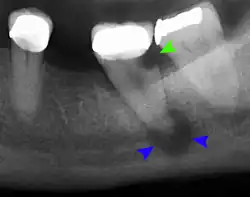

The periodontal ligament becomes inflamed and there may be pain when biting or tapping on the tooth. On an X-ray, bone resorption appears as a radiolucent area around the end of the root, although this does not manifest immediately.[10]: 228 Acute apical periodontitis is characterized by well-localized, spontaneous, persistent, moderate to severe pain.[6]: 125–135 The alveolar process may be tender to palpation over the roots. The tooth may be raised in the socket and feel more prominent than the adjacent teeth.[6]: 125–135

- Radiographs utilized to find dental caries and bone loss laterally or at the apex.

Decay (green) with apical abscess (blue) -